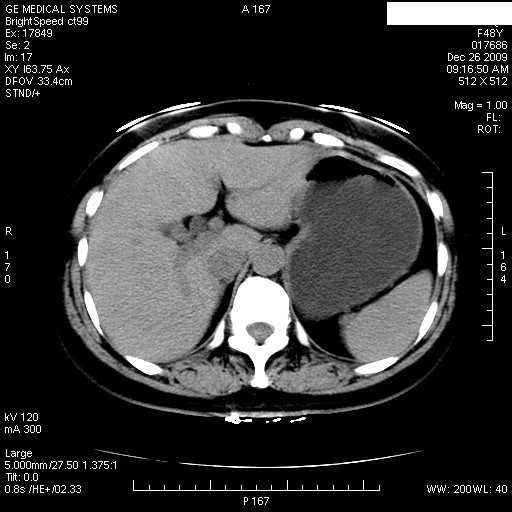

标题: CT23914:女性 48岁 上腹部疼痛1周,请求会诊 [打印本页]

标题: CT23914:女性 48岁 上腹部疼痛1周,请求会诊

患者女性 48岁 突发上腹部疼痛,无其他不适,查体莫菲氏征阴性,ct示:胆囊炎,胆总管上端轻度扩张

图片如下: